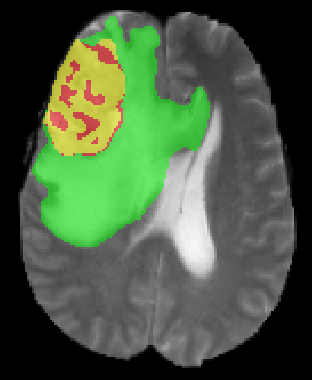

We argue that the sub-optimal paradigm of processing different abstractions within a single CNN pipeline can be remedied through the effective processing of information in a structured manner. Consequently, we devise strategies for disentangling the edge and texture information within a single training pipeline. Figure 2 illustrates how our proposed module, dubbed EG-CNN, can be paired with any existing CNN encoder-decoder to improve segmentation quality near intensity edges. We have applied our EG-CNN to the tasks of brain and liver tumor segmentation in medical images (Figure 3).

(1) Brain MR (2) Liver MR (3) Liver CT (4) Lung CT